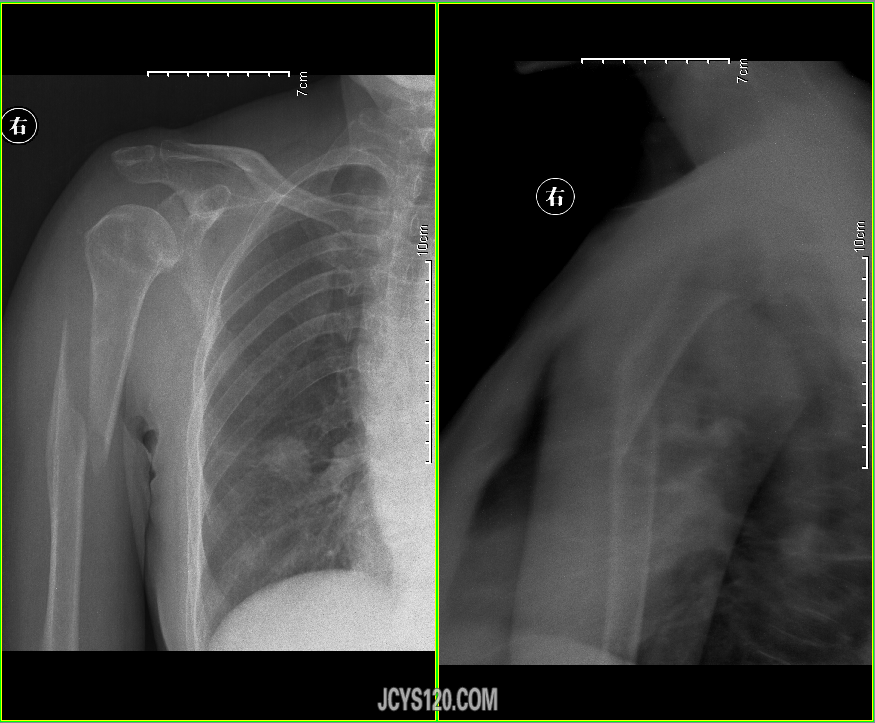

患者女,68岁,根据家属交代搬石头时肩部咔嚓一声。余病史不详。 阅读全文>